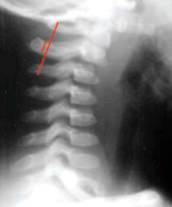

Normal lateral c-spine film 1:

Draw 4 smooth curved lines running from top to bottom vertical lines:

- The anterior vertebral bodies,

- The posterior vertebral bodies,

- The facet line,

- The spinolaminar line

Spinal column lies between 2 and 4 Lines: Smooth No steps

No angulation Line 2 should line up with the clivus; Line 4 should line up with the Back of the foramen magnum.